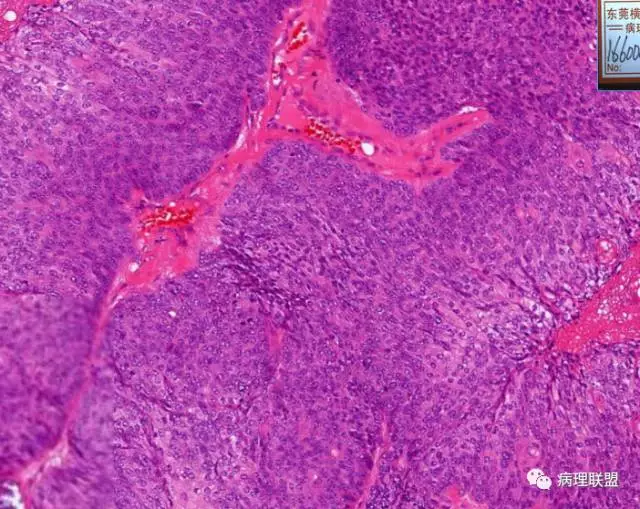

在看,突然没有了思绪。第一个有两种细胞,一种是嗜碱性胞浆的,一种是透亮的。

第一例和第二例病例我把典型图像压下来,是让我们以后注意,典型里找不典型,毛母质瘤主要由两种细胞构成,嗜碱细胞和影细胞构成,主要认识嗜碱细胞。